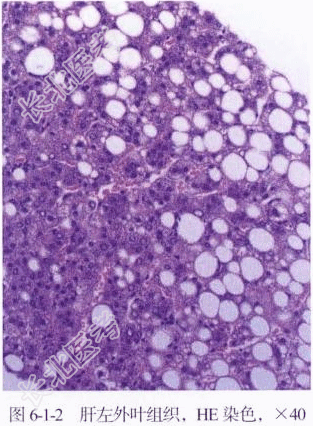

【病理所见】(肝左外叶)切面呈灰黄、灰红色,质中,相连肝组织切面可见散在灰黄色结节,直径为0.4~1.2cm,周围肝脏灰红色,质中,肝细胞排列紊乱,呈结节状,部分区域见纤维组织增生和大量脂肪细胞(图6-1-2);(肝右叶6段)切面见一灰红色区,质软,大小为5cm×4.5cm×4cm,余切面可见散在灰黄色结节,大小为0.2~1cm,局灶血管扩张、充血,灶区组织梗死。

【病理诊断】肝细胞腺瘤(多发)伴脂肪变性。